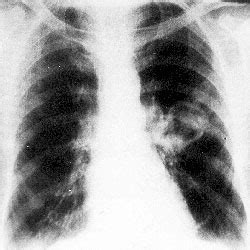

Dažniausiai hamartoma diagnozuojama 50-70 metų amžiaus žmonėms, tačiau gali būti nustatoma ir 9-20 metų pacientams. Periferinėje plaučių dalyje esanti hamartoma paprastai simptomų nesukelia. Bronchų hamartoma sutrikdo drenažinę plaučių funkciją, skatina prasidėti pneumoniją. Ligonis gali skųstis kosuliu, dusuliu, kraujo iškosėjimu, vienos plaučio dalies recidyvine pneumonija. Periferinėje plaučių dalyje esanti hamartoma krūtinės ląstos rentgeninio tyrimo metu matoma kaip intensyvus ryškių kontūrų ovalus pritemimas. Darinys dažniausiai yra nehomogeniškas. Apie 10-25 proc. atvejų jame gali būti apkalkėjimų, inkrustacijų. Jei hamartoma yra stambiame bronche, tiriant rentgenu matoma plaučio segmento ar skilties atelektazė arba sumažėjęs oringumas. Hamartomai būdingi kompiuterinės plaučių tomografijos požymiai - mažesnis negu 2,5 cm dydžio aiškių ribų „minkštos“ sienelės darinys, kuriame yra riebalų ir (ar) kalcio sankaupų. Bronchoskopuojant matomas darinys, užkemšantis broncho spindį, neinfiltruojantis aplinkinių audinių.